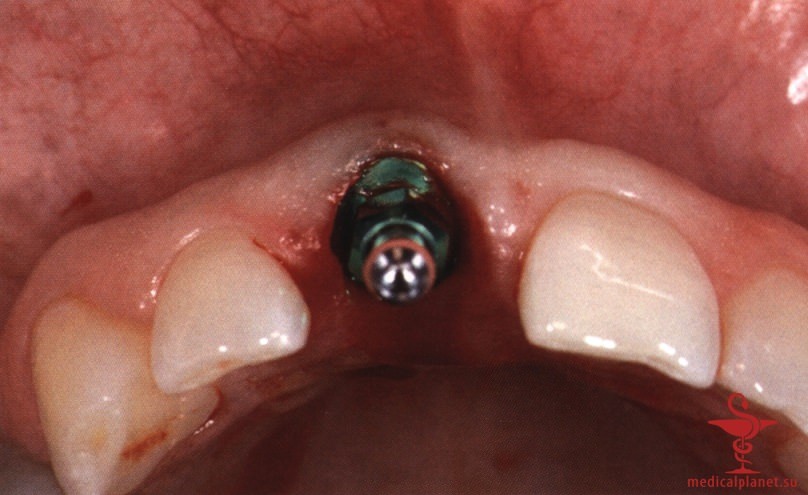

г) Положение и диаметр имплантата. Установка имплантата в лунку сразу после удаления зуба без отслаивания лоскута требует глубоких знаний и большого опыта хирурга.

Сложность такого подхода обусловлена высокой вероятностью наличия или формирования костного дефекта в области имплантации. В течение многих лет считалось, что имплантат остеоинтегрируется только при минимальном зазоре между ним и костью. Однако в 1988 г. Carlsson и соавт. описали феномен «костного прыжка», который заключается в возможности достижения остеоинтеграции даже при довольно большом расстоянии между поверхностями имплантата и кости.

Сначала предполагалось, что уменьшение зазора является предпочтительным, поэтому рекомендовали устанавливать имплантаты максимального диаметра. Данное предположение оказалось ошибочным. В настоящее время доказано, что зазор менее 0,5 мм между костью и имплантатом заполняется новообразованной костной тканью без каких-либо дополнительных манипуляций.4 Более того, следует избегать контакта имплантата с костной стенкой, чтобы не оказывать на нее давление, которое сопровождается резорбцией кости (рис. 4).